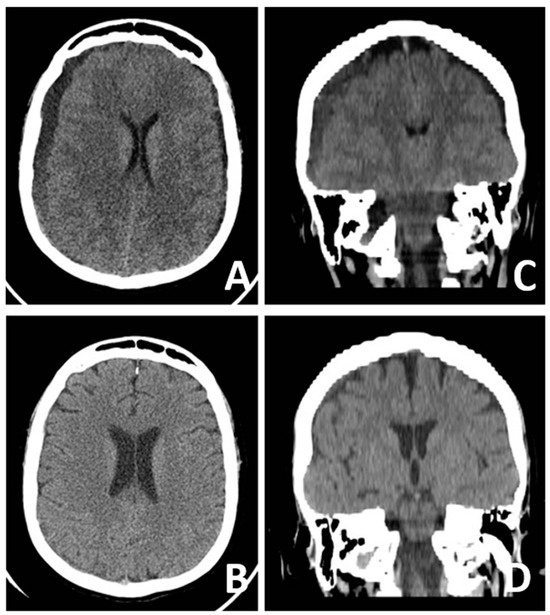

3.1. Case Presentation